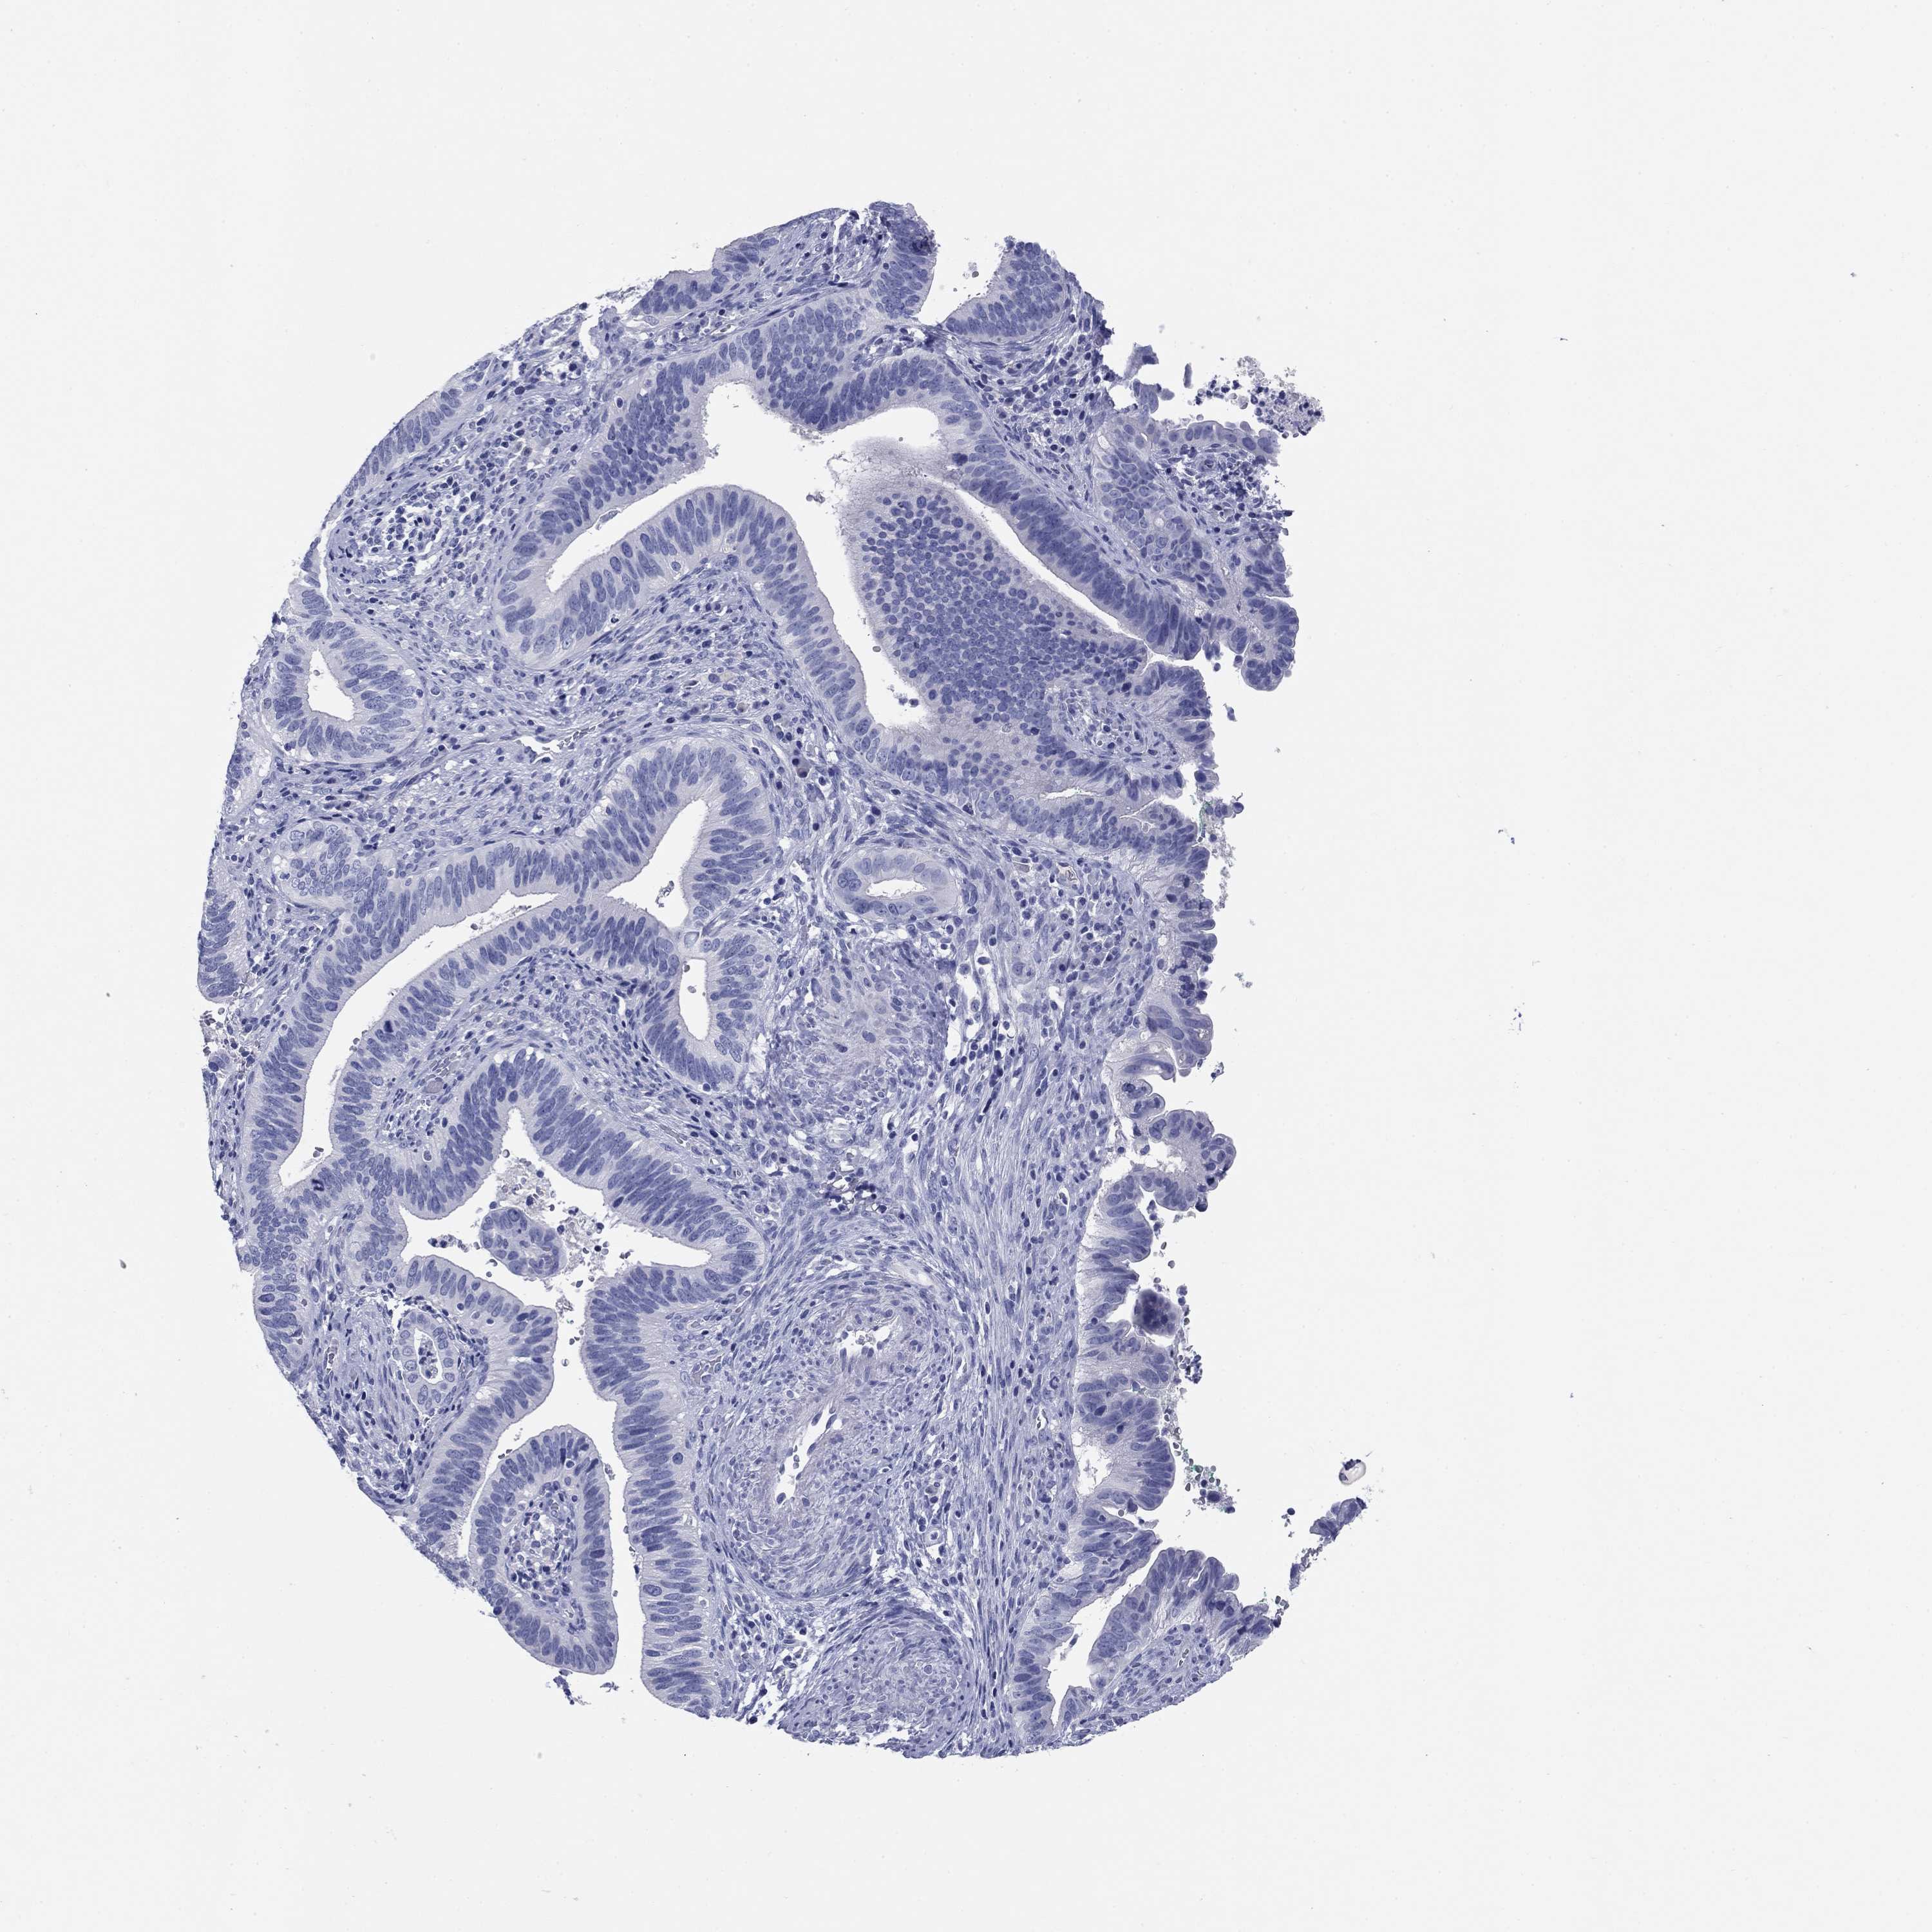

CERVICAL CANCER - Protein expressioni

A mouse-over function shows sample information and annotation data. Click on an image to view it in a full screen mode. Samples can be filtered based on level of antibody staining by selecting one or several of the following categories: high, medium, low and not detected. The assay and annotation is described here.

Note that samples used for immunohistochemistry by the Human Protein Atlas do not correspond to samples in the TCGA dataset.

Antibody stainingi

Antibody staining in the annotated cell types in the current human tissue is reported as not detected, low, medium, or high, based on conventional immunohistochemistry profiling in selected tissues. This score is based on the combination of the staining intensity and fraction of stained cells.

Each image is clickable and will lead to virtual microscopy that enables deeper exploration of all samples and also displays staining intensity scores, fraction scores and subcellular localization as well as patient and tissue information for each sample.

Antibody HPA019445

Antibody HPA076421

Staining

High

Medium

Low

Not detected

Intensity

Strong

Moderate

Weak

Negative

Quantity

>75%

75%-25%

<25%

None

Location

Nuclear

Cytoplasmic/membranous

Cytoplasmic/membranous,nuclear

Squamous cell carcinoma, NOS

Adenocarcinoma, NOS